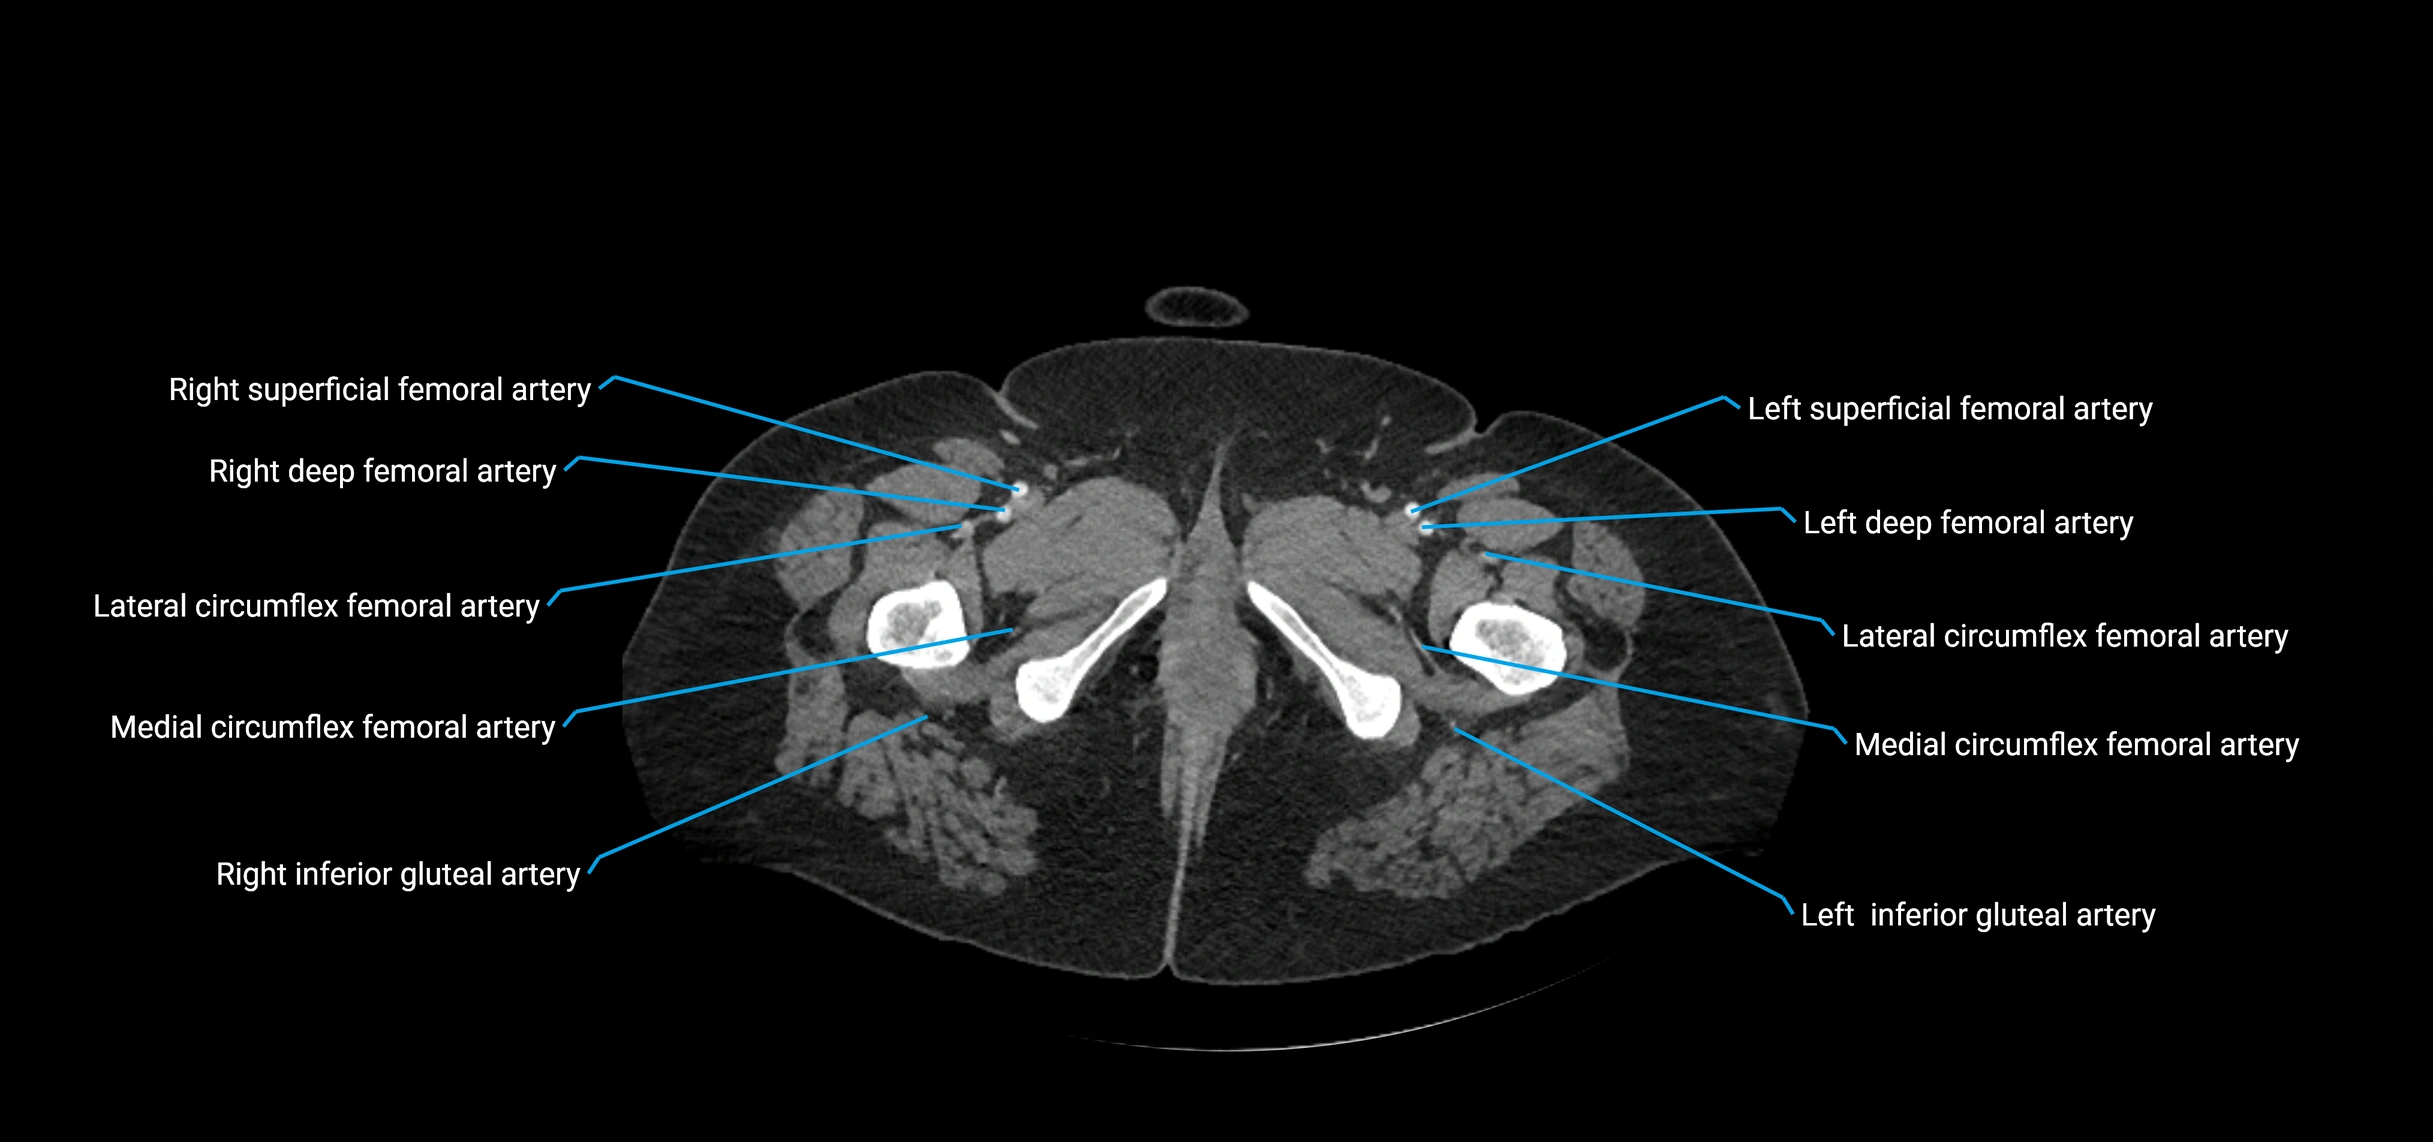

Contrast-enhanced CT (CTA):

• Gold standard for abdominal aortic imaging

• Provides excellent detail of lumen, wall, aneurysm, thrombus, and branch vessels

• Multiplanar and 3D reconstructions help in aneurysm measurement, stent graft planning, and dissection evaluation

• Detects acute rupture, traumatic injury, or occlusion with high sensitivity